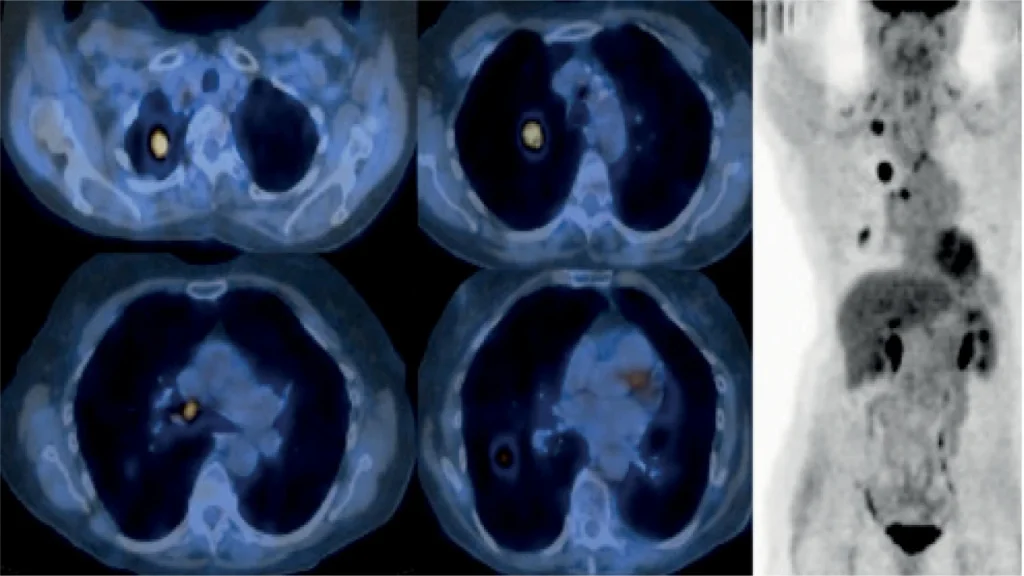

اسکن هستهای سرطان یک روش تصویربرداری پزشکی پیشرفته است که با استفاده از مواد رادیواکتیو (رادیوداروها) و دستگاههای خاص مثل گاما کمرا انجام میشود. این مواد پس از ورود به بدن، در اندام یا بافت هدف تجمع پیدا میکنند و با تابش اشعهای خاص، امکان ثبت تصاویر دقیق از عملکرد و ساختار داخلی بدن را فراهم میکنند.

در واقع، برخلاف سیتیاسکن یا امآرآی که بیشتر ساختار فیزیکی اعضا را نشان میدهند، اسکن هستهای به ما اطلاعاتی درباره عملکرد و متابولیسم بافتها میدهد.

سرطان معمولاً در مراحل ابتدایی علائم واضحی ندارد. اسکن هستهای میتواند کوچکترین تغییرات عملکردی سلولها را آشکار کند، حتی قبل از آنکه این تغییرات در تصاویر ساختاری مشخص شوند. این ویژگی باعث میشود:

1. تجهیزات پیشرفته و فناوریهای روز دنیا

یک مرکز معتبر باید به دستگاههای مدرن مثل گاما کمرا و PET/CT مجهز باشد. استفاده از فناوریهای جدید باعث افزایش دقت تصاویر، کاهش خطاهای احتمالی و تشخیص سریعتر بیماری میشود.